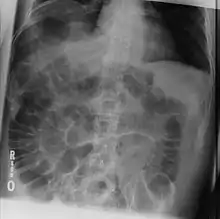

The dark areas on both sides of the intestines indicate that air is present in both sides. This is called "Rigler's sign".